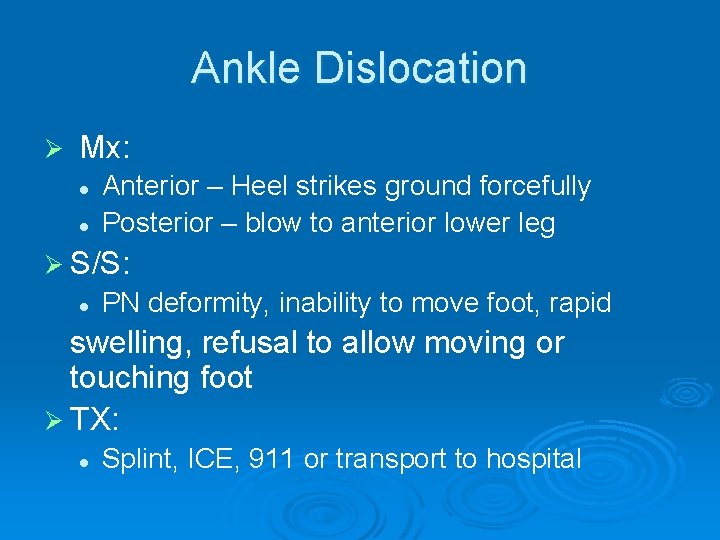

Ankle Dislocation Ø Mx: l l Anterior – Heel strikes ground forcefully Posterior – blow to anterior lower leg Ø S/S: l PN deformity, inability to move foot, rapid swelling, refusal to allow moving or touching foot Ø TX: l Splint, ICE, 911 or transport to hospital